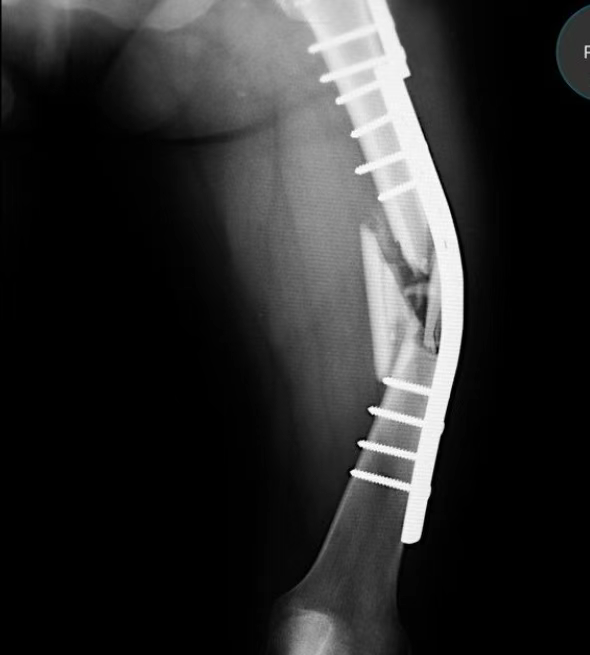

After fixation of the distal end of the radius for 1 week, the patient felt hand rotation disorder, and radiographs revealed anterior dislocation of the radial head. A second-stage operation was performed to reconstruct the proximal oblique cord of the interosseous membrane: